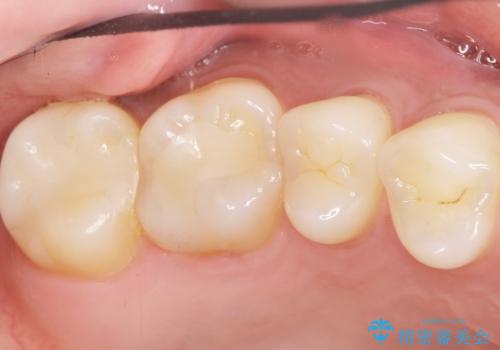

不適合なレジンを除去し、セラミックインレーによる治療を行いました。(右上76左上67右下7の計5本)

気にされていたフロスをした時のにおいがなくなり、喜んで頂けました。

治療終了後半年のメンテナンス時には「咬み合わせもばっちりです!」とおっしゃって下さいました。

インレーの種類:セラミックインレー e-max press